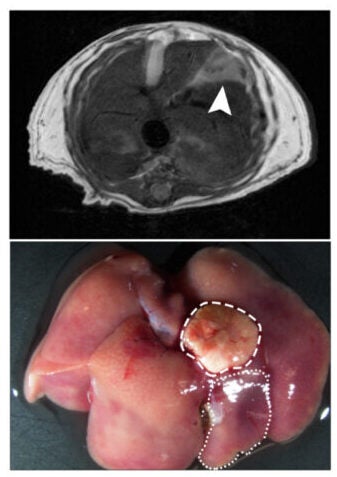

To understand what a high-fat diet does inside the liver, the team used mice and fed them a diet designed to trigger disease through food alone. They then tracked changes over months as the liver moved from fat buildup to inflammation, then scarring, and finally spontaneous tumors.

Across the mouse timeline, nearly all animals on the high-fat diet developed liver cancer by the end of the study. The researchers say the shift toward an immature state helps explain why. Once cells lose parts of their mature identity, they can become more willing to divide and less constrained by the usual rules of liver function.

Sequencing results suggested that losing HMGCS2 pushed hepatocytes further along the stress path, making their gene patterns look more “advanced” than diet alone. When the researchers used a tumor-triggering system during chronic dietary stress, the HMGCS2 knockout mice developed greater tumor outgrowth and larger nodules.